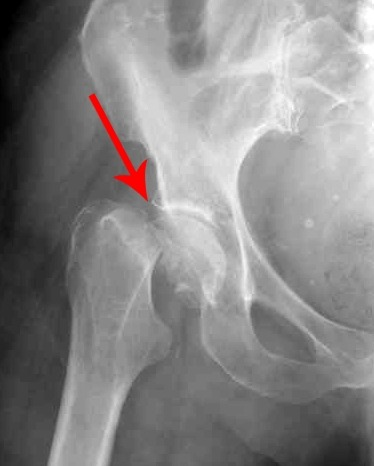

Перелом шейки бедра рентген.